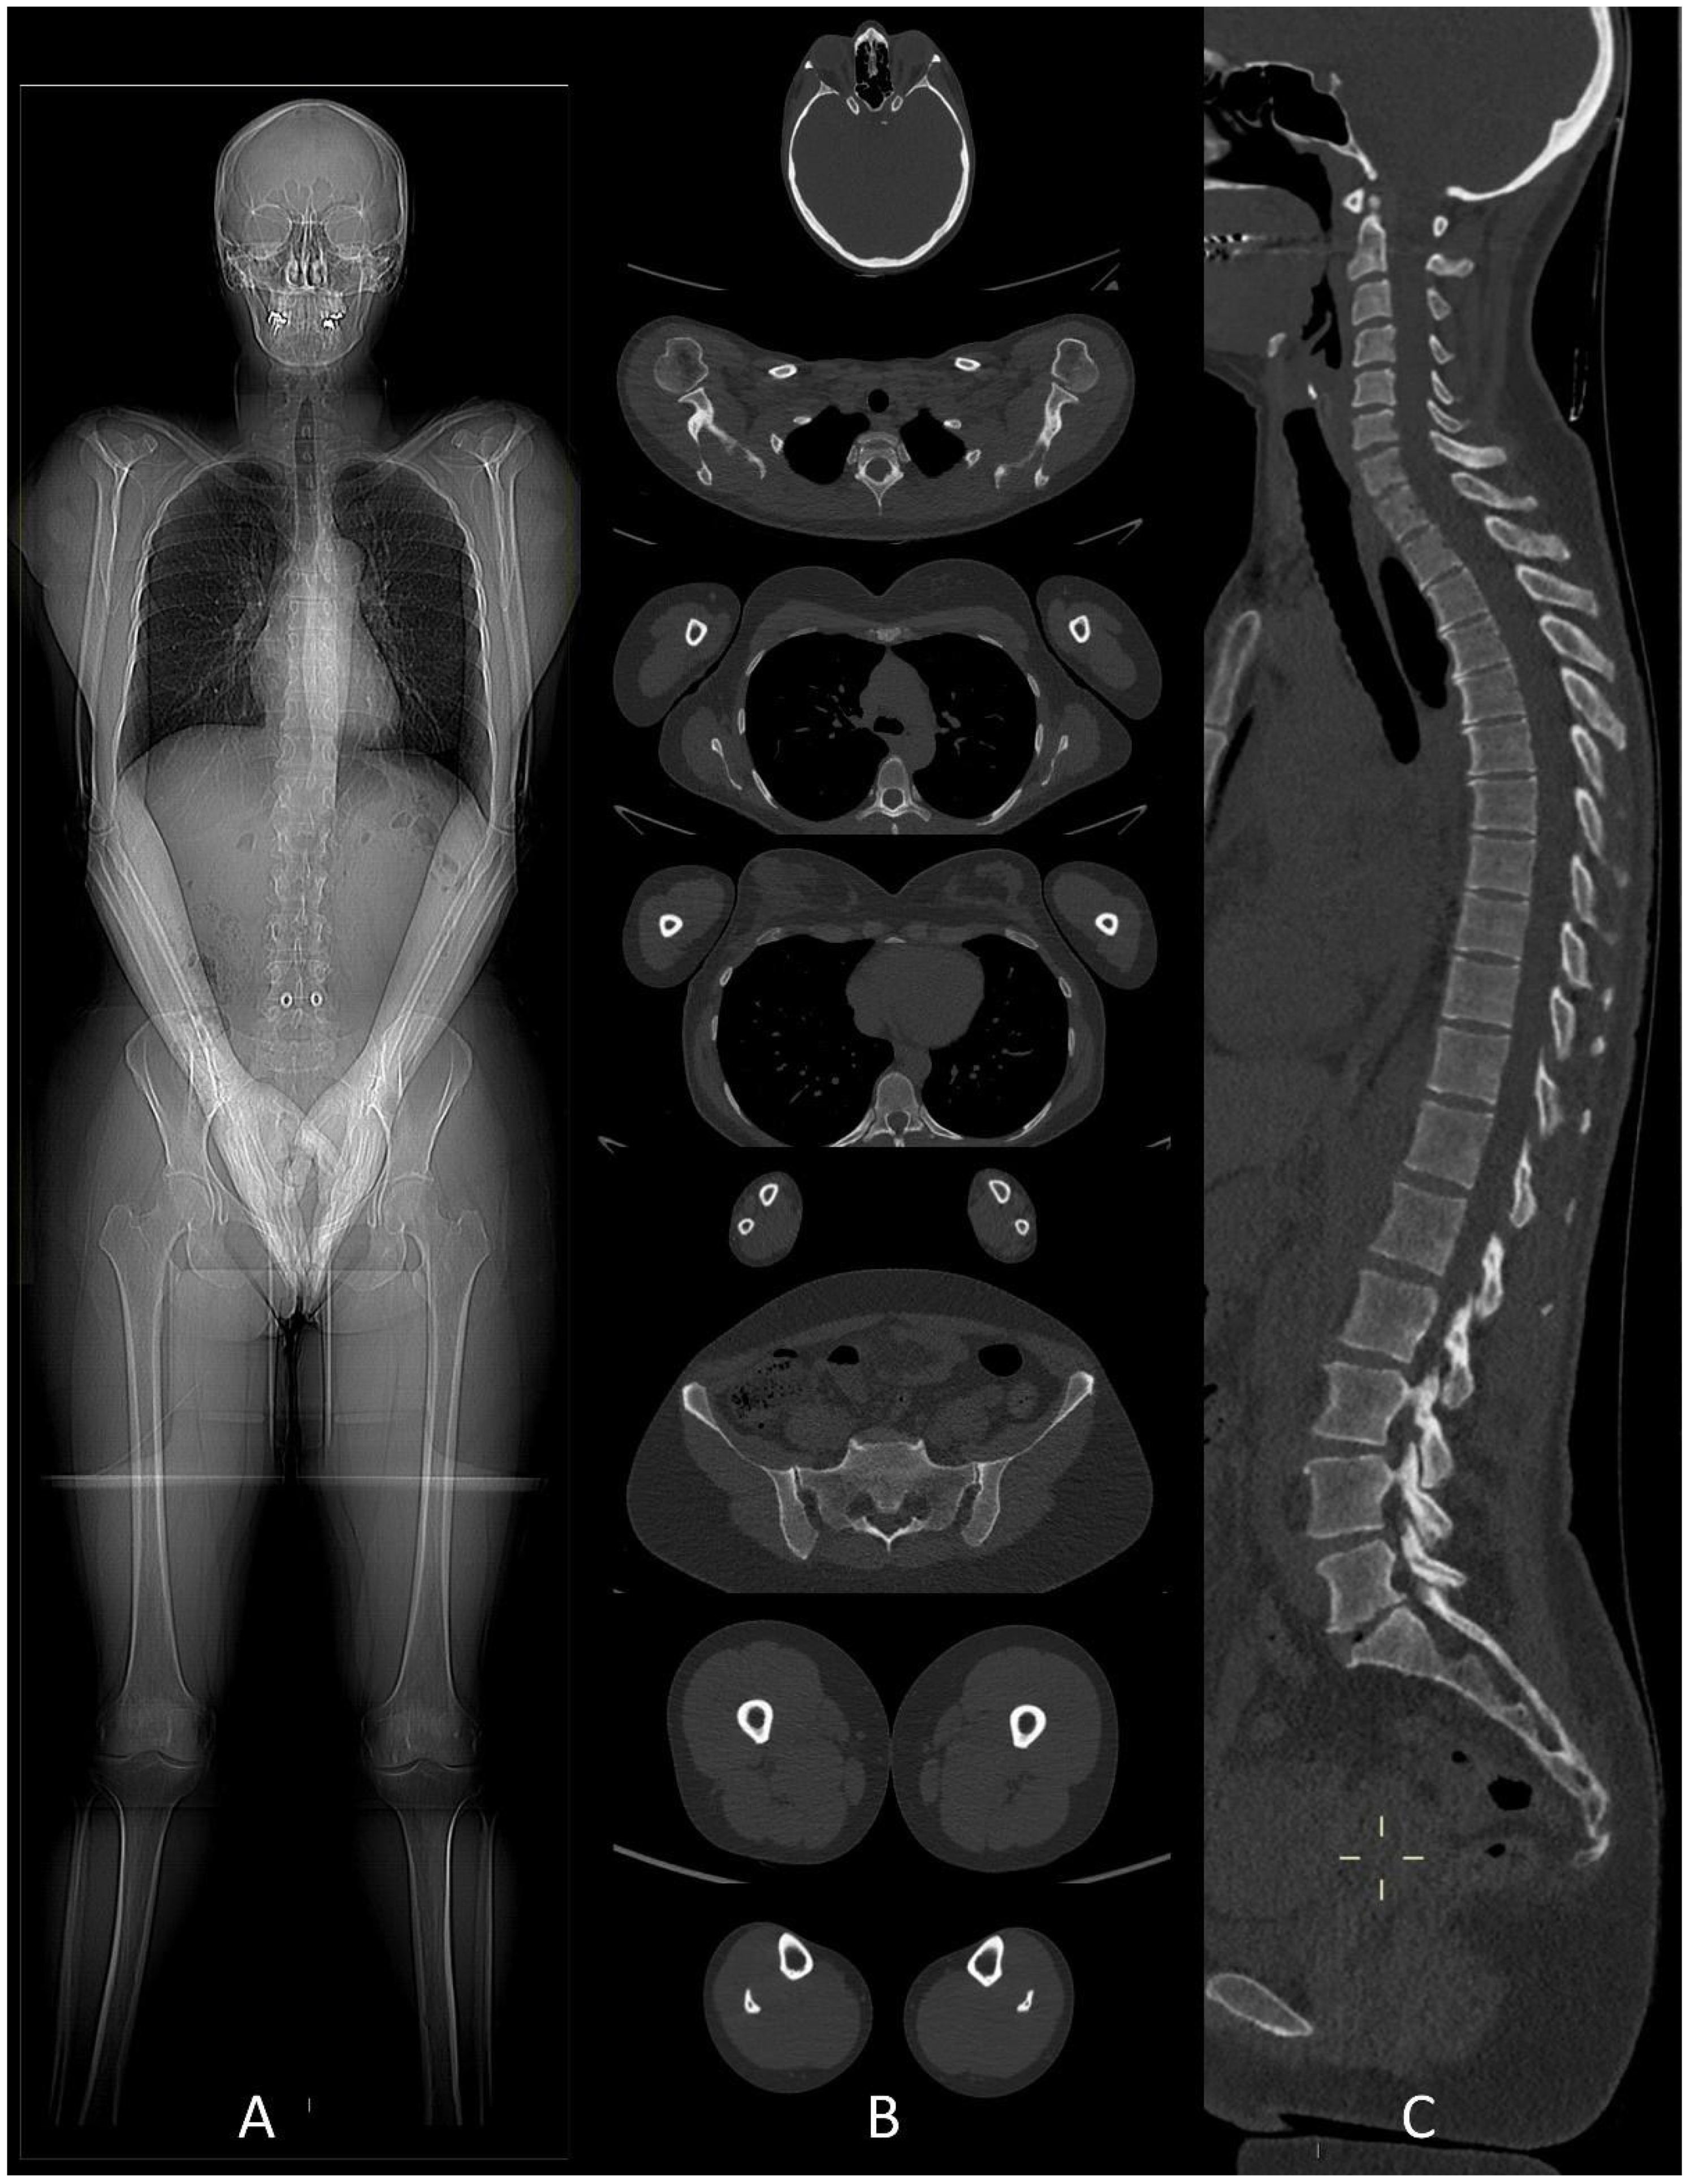

Whole-body low-dose CT examinations are performed without any preparation nor contrast agent. The patient stays in the supine position assuring that limbs are in the field of view. The upper limbs must be in front position, above the abdomen with the hands joined (Figure 1), to avoid the image having poor quality due to streak artifacts generated by beam hardening on the spine [15].

Figure 1.

(A) CT scout-view showing the correct patient position in the CT scanner to avoid beam-hardening artifacts on thoracic and lumbar spine. (B) Whole-body low-dose CT examination performed from the skull down to the lower limbs. (C) Sagittal CT image showing cervical, dorsal and lumbar spine with “bone” algorithm is the best plane to identify vertebral compression fractures.

Axial images using a “bone” reconstruction algorithm must be systematically performed, usually in a cranio-caudal fashion, starting from the skull to the cervical, thoracic, and lumbar spine, pelvic bones, and lower limbs, whereas ribs, sternum, scapulae, clavicles, and upper limbs are evaluated afterward (Figure 1B). Once completed, it is advisable to analyze the sagittal multiplanar reconstruction (MPR) images of the spine to identify vertebral fractures and to assess the risk of neural compression (Figure 1C). MPR images are also useful to differentiate benign osteoporotic vertebral fractures from malignant ones (although MRI remains the gold standard for differential diagnosis of vertebral collapse): predictive CT findings of benign vertebral fractures are the presence of fracture lines within vertebral body, retropulsion of a bone fragment from posterior wall into the spine canal, evidence of paraspinal soft tissue widening, and intravertebral “vacuum sign” defined as the presence of an air cleft in the vertebral body. Features associated with malignant vertebral fracture are the presence of extended destruction of the vertebral body (cortex and cancellous bone) and pedicles, as well as a focal soft tissue mass in the paravertebral or epidural space [15]. Focal and/or diffuse intra-medullary infiltration of femur and humerus can be found by analyzing axial and MPR images (Figure 2 and Figure 4) [22].